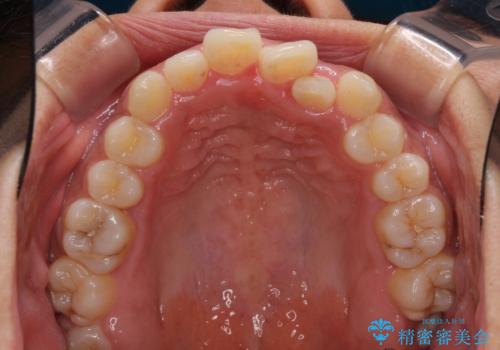

- 上下前歯の叢生を気にして来院された患者様です。

2年ほどインビザライン矯正を続けましたが、終了することができず、ワイヤーへ転換後は1年弱で終えることができました。